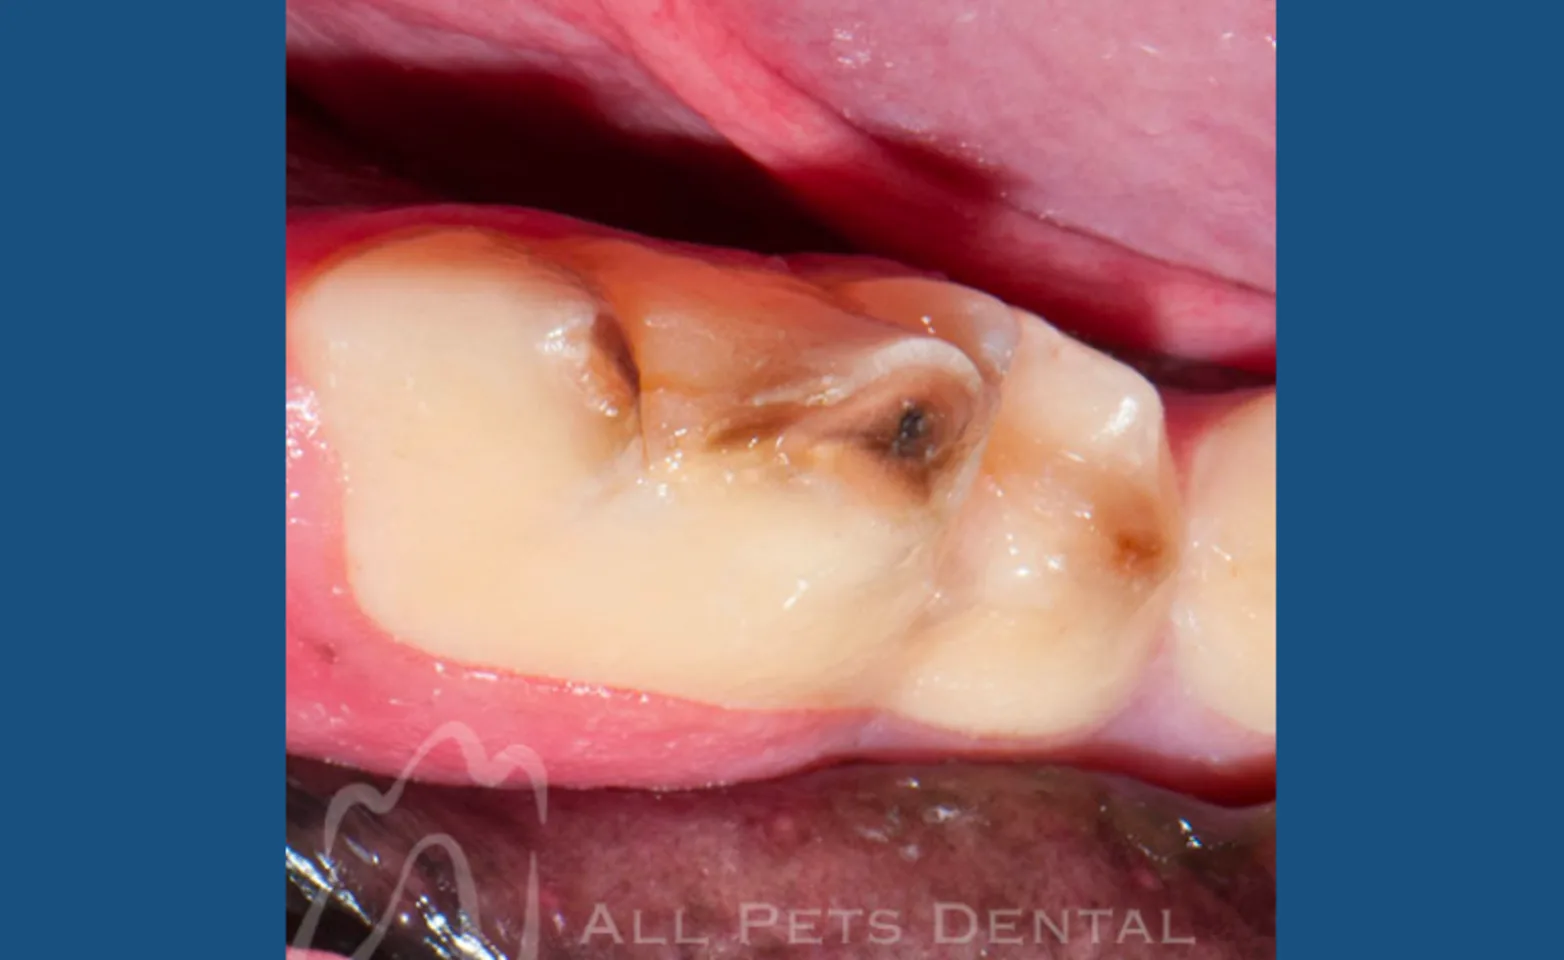

Uncomplicated Crown Fracture

Uncomplicated crown fractures do not directly expose the tooth’s pulp (nerve). Nonetheless the tooth may be sensitive and should be treated.

Complicated Crown Fracture